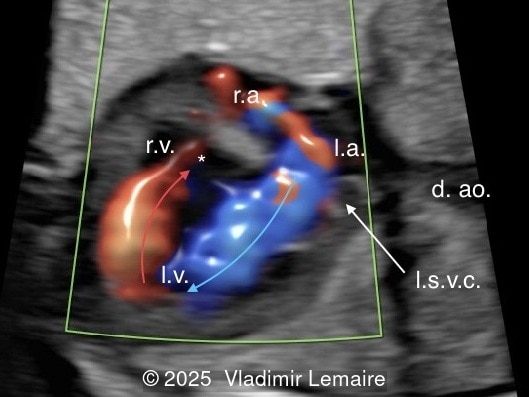

We present a case of isolated tricuspid atresia type 1 with persistent left superior vena cava. No other extracardiac anomalies were found. Our diagnosis was confirmed after birth.

In the images below, the abbreviations are as follows: RA: right atrium; RV: right ventricle; LV: left ventricle; MV: mitral valve; LA: left atrium; FO: foramen ovale; SVC: superior vena cava; LSVC: left superior vena cava; PV: pulmonary veins; PA: pulmonary artery; MPA: main pulmonary artery; RPA: right pulmonary artery; AO: aorta; dAO: descending aorta; aAO: ascending aorta; DA: ductus arteriosus; T: trachea; * marks the ventricular septal defect.

Color Doppler confirms the diagnosis on grayscale ultrasound, as it demonstrates the lack of blood flow across the tricuspid valve and a patent mitral valve. Due to increased blood flow across the mitral valve, aliasing is typically noted on color Doppler. Mitral valve regurgitation has been associated with a poor outcome. The right ventricular cavity is filled in late diastole from the left ventricle, through the ventricular septal defect. Left-to-right shunting across the ventricular septal defect can be seen on color Doppler. Color Doppler is helpful in the evaluation of flow across the great arteries. Flow across the pulmonary artery is generally antegrade. Pulmonary stenosis should be suspected when the vessel is diminutive in size rather than the demonstration of turbulent flow on color Doppler, which is typically absent in these cases.

Flow across the ductus arteriosus is usually antegrade. The demonstration of retrograde flow in the arterial duct is a sign of ductal-dependent pulmonary circulation with possible cyanosis in the newborn. Ductal-dependent pulmonary circulation in tricuspid atresia is seen in severe pulmonary stenosis or atresia in association with a small right ventricle.